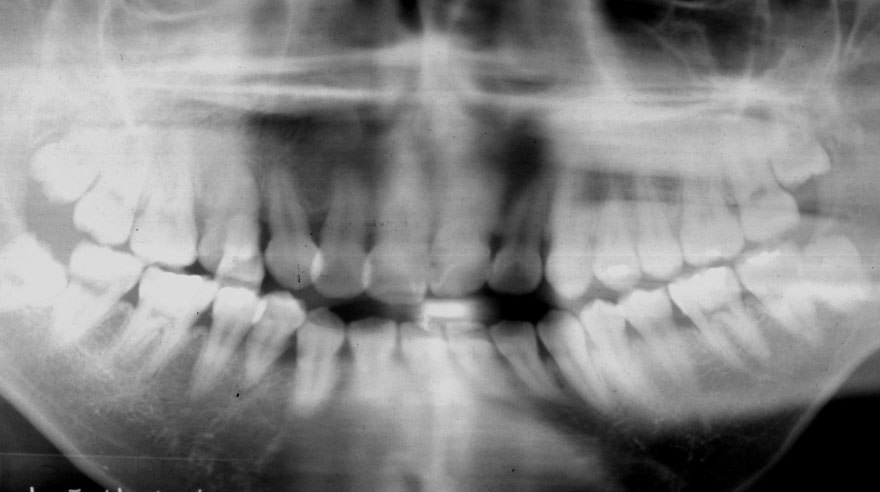

初診時 29歳 男性

河田歯科医院

30年後 59歳